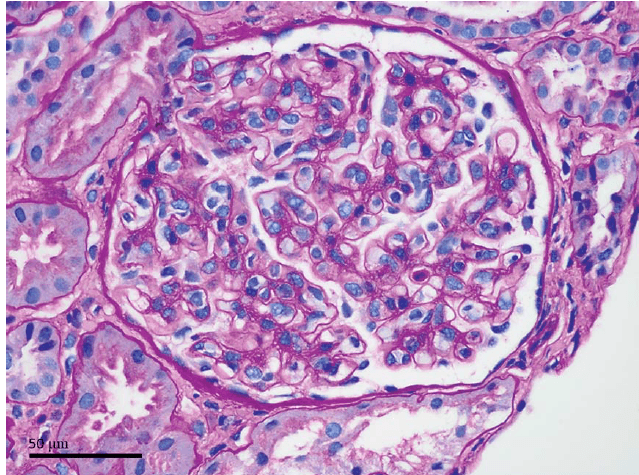

Realizado investigação da atividade de renina plasmática e do nível sérico de aldosterona que foram 8,4 ng/mL por hora e 18 ng/dL, respectivamente. O uso de losartana normalizou a pressão arterial. Imagens subsequentes mostraram evolução para atrofia cortical do parênquima previamente isquêmico (Fig. 1C, seta). Após vários meses, sua pressão arterial voltou ao normal; a losartana foi descontinuada.

(A) Uma tomografia computadorizada pré-procedimento do abdômen e pelve com contraste intravenoso com rins simétricos (seta). (B) Tomografia computadorizada do 6º dia pós-cirúrgico com uma nova região se hiporealce na região inferior polo do rim esquerdo consistente com hipoperfusão/infarto renal (seta). (C) Tomografia computadorizada 5 meses após a cirurgia com atrofia focal do polo inferior do rim esquerdo (seta).